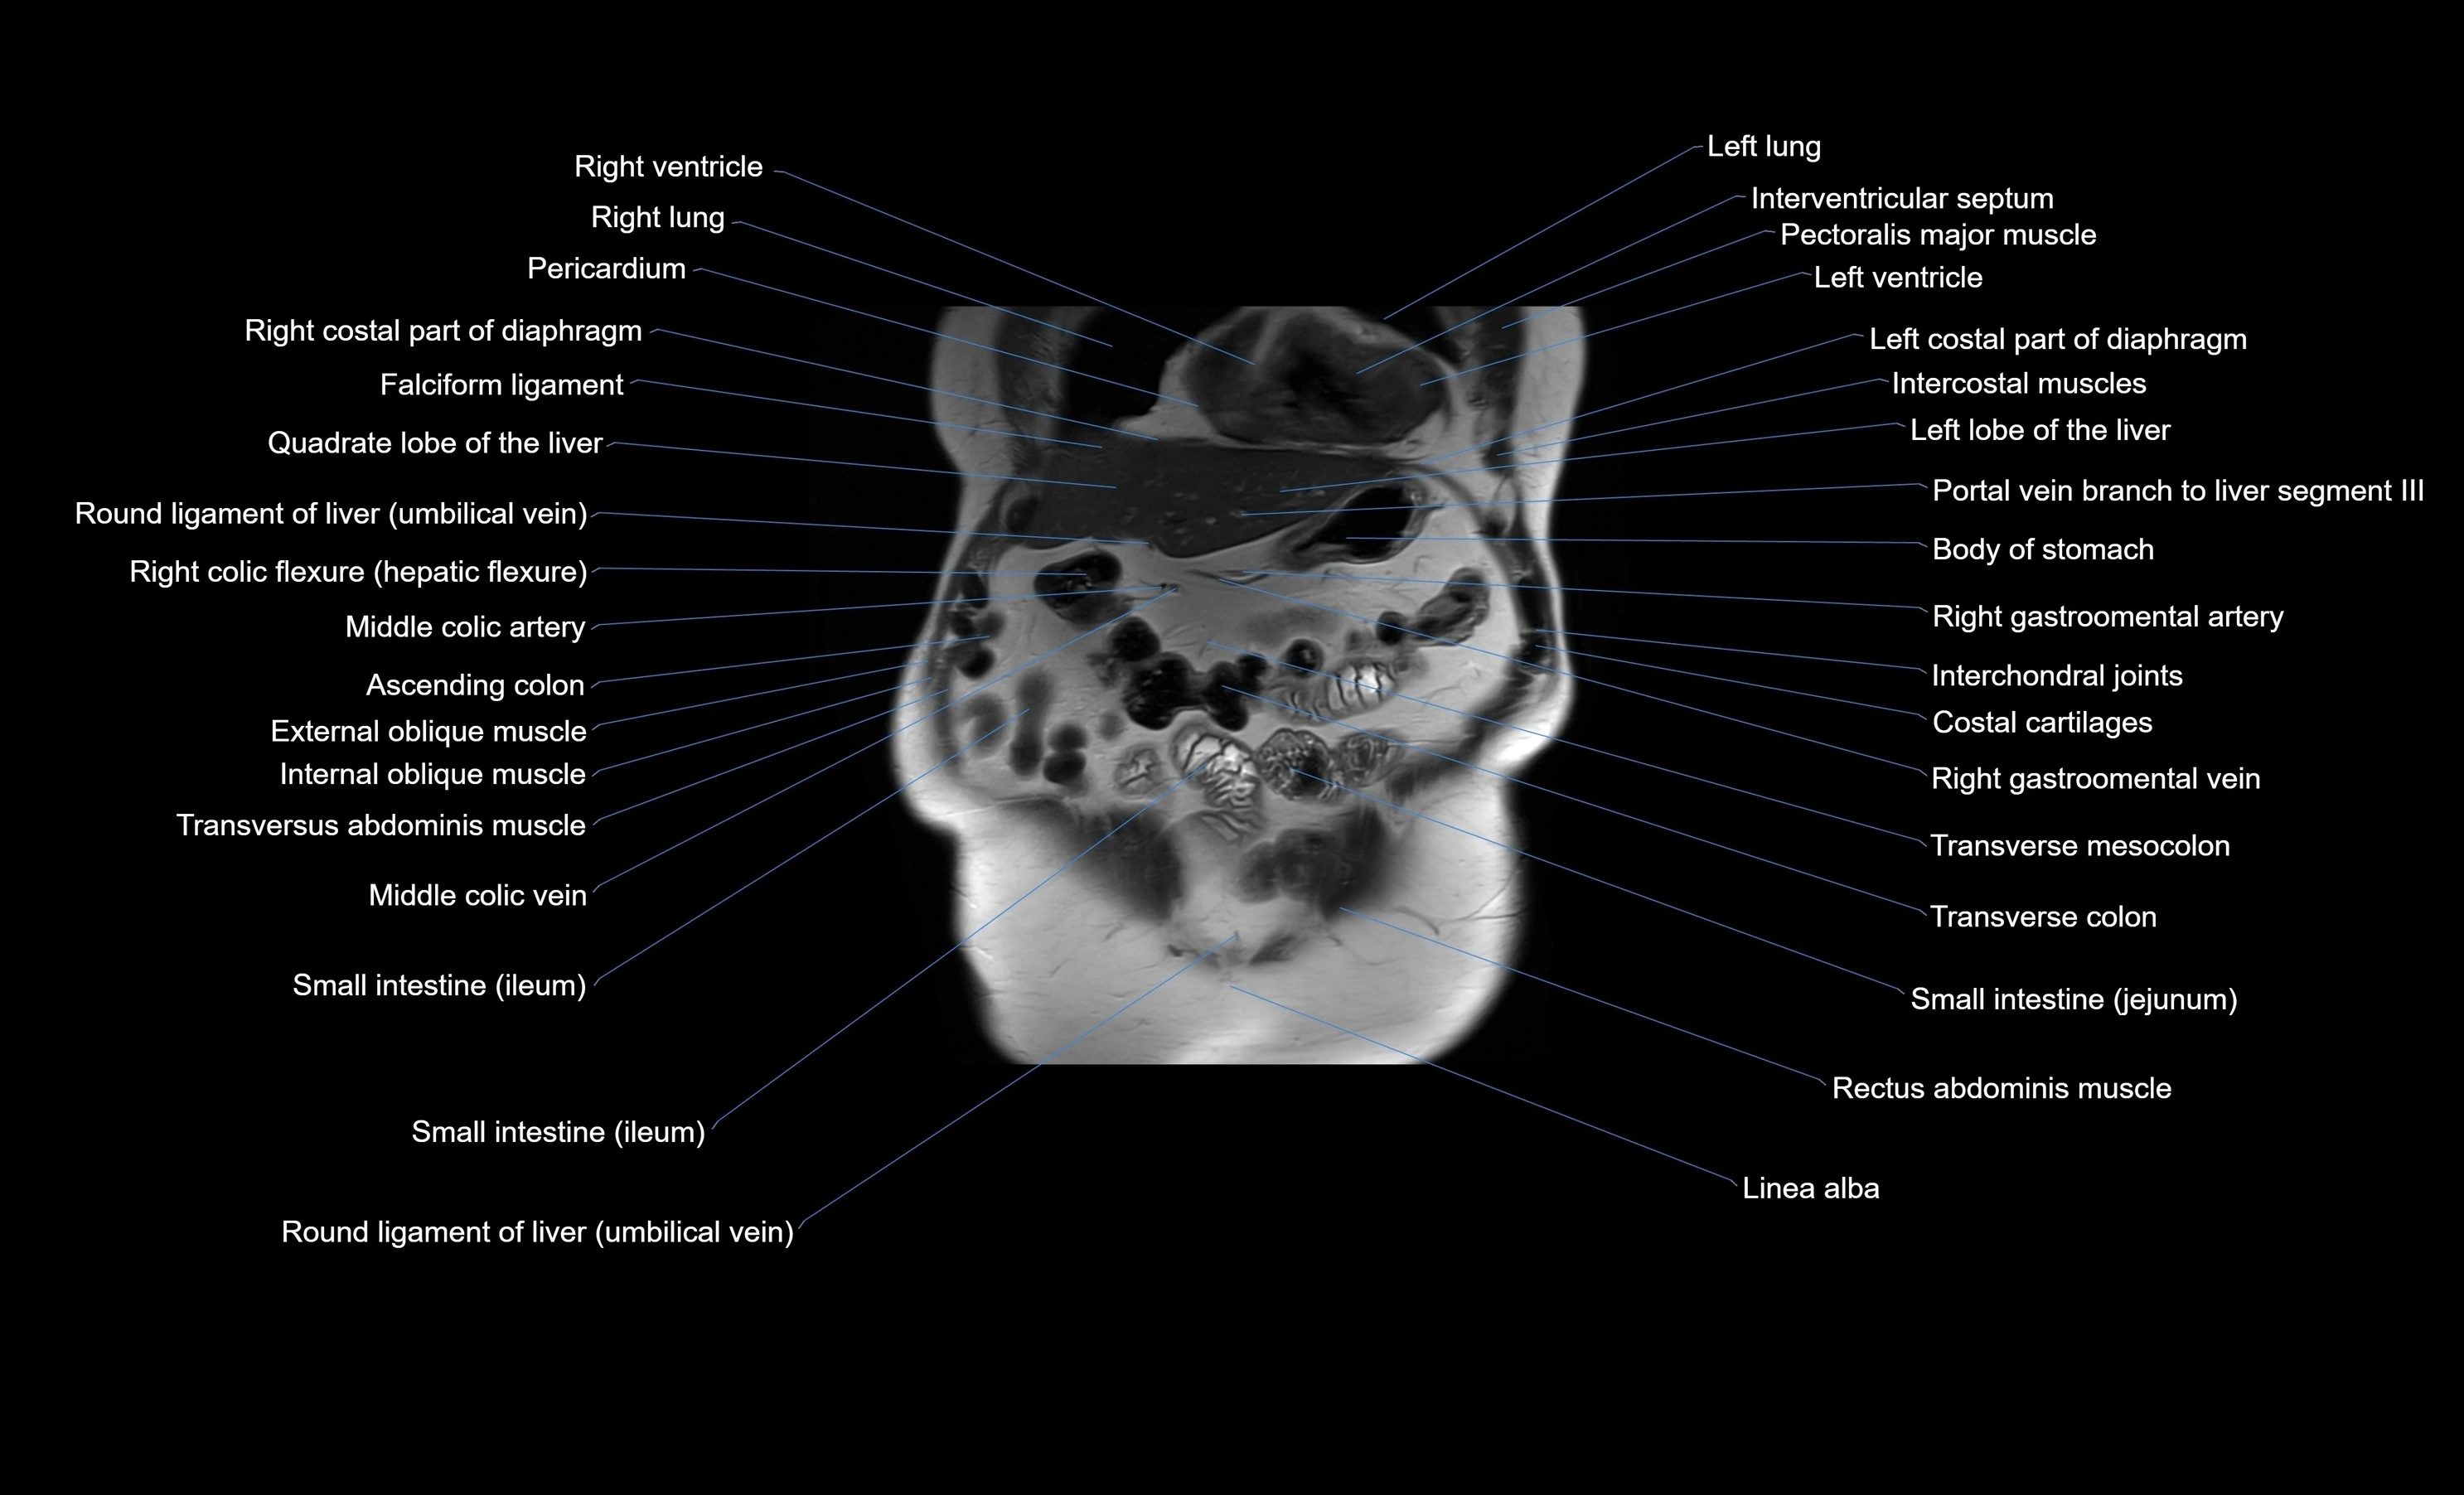

MRI images